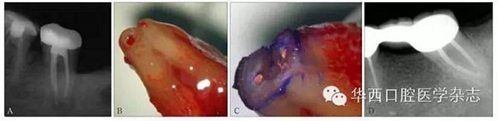

X線根尖片在牙髓診斷中常用來(lái)確定工作長(zhǎng)度,經(jīng)驗(yàn)性地認(rèn)為,根尖止點(diǎn)距影像學(xué)根尖的距離為0.5~1 mm。但X線根尖片具有輻射危害、較長(zhǎng)的拍片時(shí)間、不確定的放大率、觀察者在讀片上主觀評(píng)價(jià)的偏移以及二維圖像代替三維圖像造成影像重疊等自身局限性[15,20-21]。此外,X線根尖片的拍攝過(guò)程具有技術(shù)敏感性,球管射線和根尖形狀、方向的關(guān)系,膠片感光度以及觀察條件等,均能影響X線根尖片測(cè)量工作長(zhǎng)度的準(zhǔn)確性[2](圖4)。研究[22]表明,多張X線根尖片結(jié)合比單張?jiān)u價(jià)時(shí)更準(zhǔn)確,而在一些復(fù)雜根管治療時(shí),如C型根管系統(tǒng),由于其根管系統(tǒng)的復(fù)雜型,X線根尖片對(duì)確定其工作長(zhǎng)度的價(jià)值不大(圖5);而當(dāng)根尖段存在不規(guī)則吸收以及吸收為頰舌向時(shí),以X線根尖片測(cè)量工作長(zhǎng)度時(shí),容易造成根管超填[2]。但X線根尖片作為術(shù)前檢查具有必要性,它可提供患牙根尖周狀態(tài)、牙根解剖形態(tài)以及鄰近解剖結(jié)構(gòu)的信息[20],可對(duì)工作長(zhǎng)度進(jìn)行初步估計(jì)。

A:42牙術(shù)前X線根尖片示根充至距影像學(xué)根尖0.5~1 mm內(nèi);B:顯微外科根尖手術(shù)術(shù)中切除根尖,體視顯微鏡 × 40。藍(lán)色箭頭示根尖段根管內(nèi)殘留壞死牙髓組織及感染物質(zhì),黑色虛線示根尖段根管,紅色箭頭示原牙膠充填止點(diǎn)。

圖4 X線根尖片未準(zhǔn)確指示根管工作長(zhǎng)度

A:37牙術(shù)前X線根尖片示根充至距影像學(xué)根尖0.5~1 mm;B:37牙行意向性牙再植術(shù),拔出后可見(jiàn)根尖牙膠超填,解剖學(xué)根尖孔距解剖學(xué)根尖有一定距離;C:截取根尖3 mm,甲苯胺藍(lán)染色示C型根管;D:47牙根管治療10年回訪,X線根尖片顯示,雖充填物距離影像學(xué)根尖約3 mm,但愈后良好。

圖5 X線根尖片評(píng)估復(fù)雜根管系統(tǒng)根管工作長(zhǎng)度存在局限性